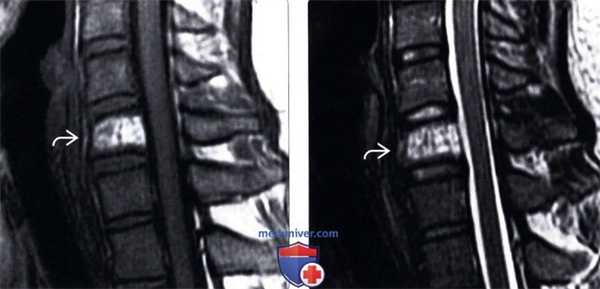

(Слева) На аксиальной МРТ (Т2 ВИ) отчетливо определяются ожидаемые признаки гемангиомы позвонка. В изоинтенсивном объемном образовании ограниченным телом позвонка, визуализируются трабекулы и жировая ткань.

(Справа) На сагиттальной MPT (STIR) определяется полное подавление сигнала в типичной гемангиоме, целиком представленной жировой тканью. Картина гемангиомы на Т2 ВИ вариабельна и зависит от жировых и сосудистых элементов.

(Слева) Сагиттальный срез, Т1-ВИ шейного отдела позвоночника: гиперинтенсивность сигнала тела С6позвонка, представляющая собой гемангиому.

(Справа) Сагиттальный срез, Т2-ВИ: у этого же пациента определяется гемангиома тела позвонка, характеризующаяся диффузной гиперинтенсивностью сигнала. Вертикальная исчерчен -ность тела позвонка соответствует утолщенным костным трабекулам, которые при данных образованиях хорошо видны на КТ.